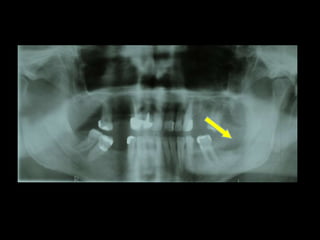

TC 3D

Adquisición de datos Reconstrucción virtual del modelo 3D Validación Validación Producción física del modelo Cirugía de modelo: moldeo placa, osteotomía mandíbula y peroné Esterilización: placa y modelo Uso en quirófano

Adquisición de datos Reconstrucción virtual del modelo 3D Validación Validación Producción física del modelo Cirugía de modelo: moldeo placa, osteotomía mandíbula y peroné. Esterilización: placa y modelo Uso en quirófano